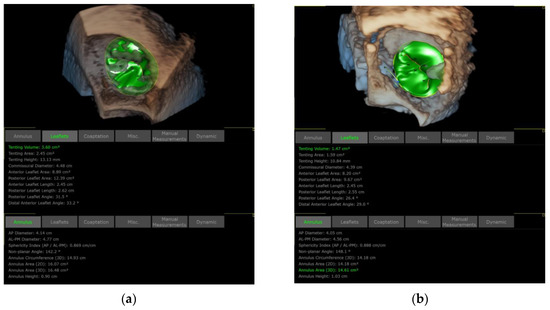

3.1. Patient Selection